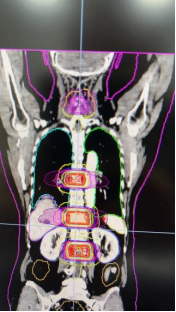

据了解,TOMO是目前国际尖端的肿瘤放疗设备,作为全球唯一采用放疗加速器与CT同源的影像引导放疗系统,突破了传统加速器的诸多限制,在CT引导下可以360°聚焦,全方位断层扫描照射,一次完成骨转移瘤多个靶区同时照射;在治疗过程中可以对肿瘤进行动态跟踪定位,减少靶区漏照,增加肿瘤控制,从而实现对复杂及晚期肿瘤更高效、精准、安全的治疗。

放疗前,治疗师团队为患者进行了头颈胸腹全体位的发泡垫固定体位,并使用了四维CT扫描定位,这种联合固定方式和动态扫描定位在保证舒适性的前提下,最大程度地减少位移与误差,保证放疗的精准性。

首次治疗当天,中大五院肿瘤中心放疗团队通力合作,患者躺在病床上仅20分钟,就完成了跨度达140cm的多个靶区的一次性精准放疗。患者开心地表示从未想到放疗可以如此迅速和舒适。

曾奇主任介绍,相较于传统放疗计划,TOMO放疗计划的靶区在适型性方面有着明显的优势。杨阿姨的治疗只用了一个照射计划就完成四个靶区的放疗,可减少多次摆位产生的误差,亦可解决拆分治疗衔接处剂量不均匀的问题,这种全新的治疗模式为患者提供了更轻松的体验。